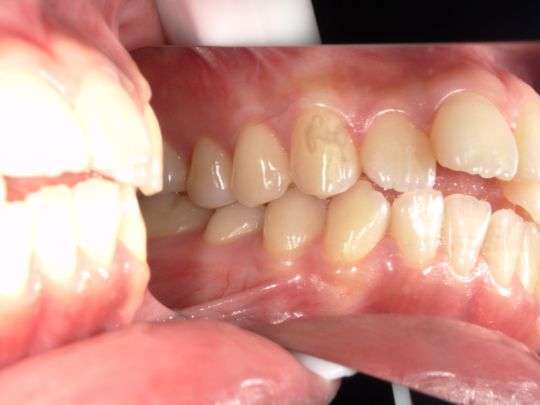

実例写真①

矯正前(横から見たところ)

矯正後(横から見たところ)